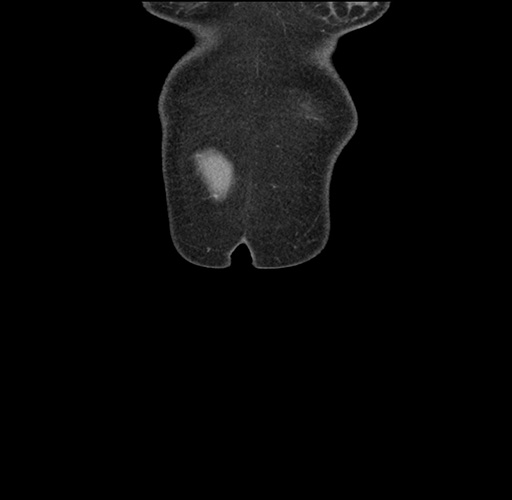

Imaging Analysis

Look through the patient's CT scan to identify any areas of concern for the necessary procedure.

Based on your CT findings, which issue(s) would give reason for "planned slowing down moment(s)" in this case?